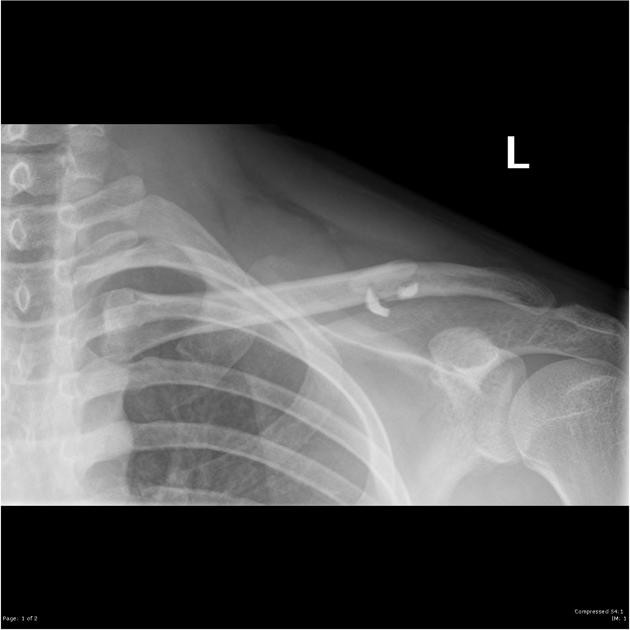

X-rays

Used to:

- Confirm the fracture

- Identify the fracture location

- Assess displacement

Regular follow-up X-rays are done to monitor bone healing.